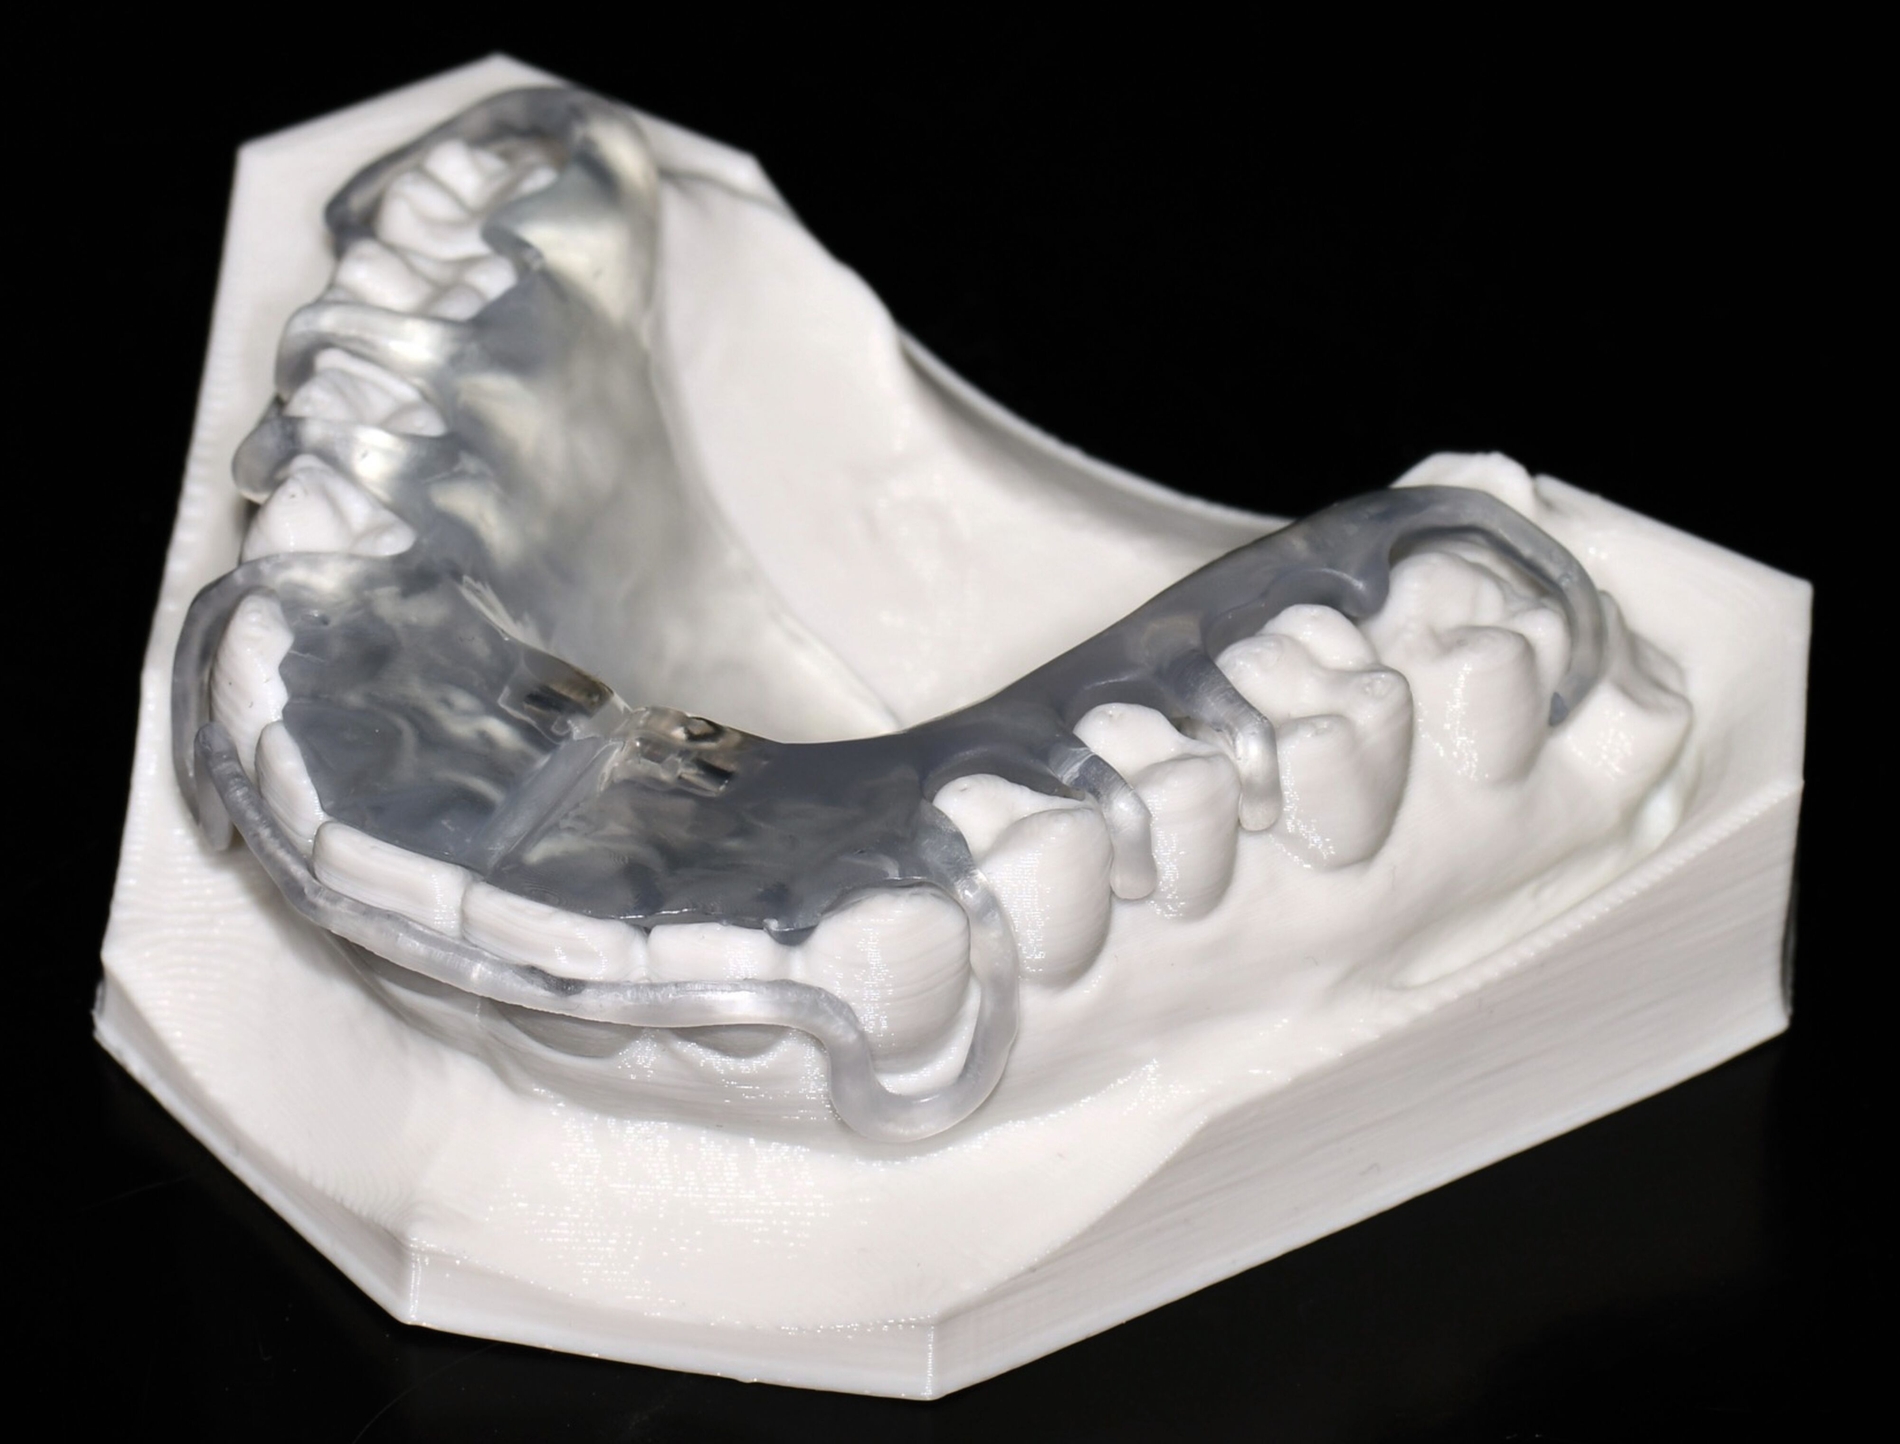

Als hochinnovatives Feld hat sich auch die Herstellung herausnehmbarer Apparaturen im 3-D-Druck entwickelt (Abbildung 4), beschränkt sich jedoch noch auf einzelne Forschungsansätze [Al Mortadi et al., 2012; van der Meer et al., 2016; Graf et al., 2022; Keller et al., 2022]. Intensiv an neuen Konzepten in der Herstellung 3-D-gedruckter herausnehmbarer Apparaturen wird am Universitätsklinikum Heidelberg geforscht. Da herausnehmbare kieferorthopädische Apparaturen im Regelfall bei jungen Patienten eingesetzt werden, kommt dem Vorteil einer unbegrenzten Replikation und einer kostengünstigen und schnelleren Herstellung ein besonderer Stellenwert zu.

Im Unterschied zu konventionellen Apparaturen bestehen die 3-D-gedruckten Apparaturen vollkommen aus Kunststoff. Eine Einarbeitung metallischer Elemente nach dem 3-D-Druck ist möglich [Al Mortadi et al., 2012; Al Mortadi et al., 2024], erfordert jedoch zusätzlichen Zeitaufwand. Zur Herstellung herausnehmbarer Apparaturen eignen sich konventionelle praxisinterne 3-D-Stereolithografie-Drucker, die in vielen Fällen bereits im regulären Praxisalltag zum Modelldruck verwendet werden. Die verwendeten Kunststoffe sollten dabei eine Klasse-IIa-Zertifizierung aufweisen, so dass ein sicherer langfristiger intraoraler Einsatz der Apparatur gewährleistet ist. Weiter muss die Apparatur nach dem 3-D-Druck gemäß den Herstellerangaben nachprozessiert werden. Im Regelfall beinhaltet dieser Prozess ein Waschen in Isopropylalkohol (IPA) sowie eine Nachhärtung im Lichthärtegerät. Eigens durchgeführte Studien sowie die bisherige klinische Erfahrung bestätigen eine hohe mechanische Stabilität, eine hohe Passgenauigkeit sowie eine breite Akzeptanz der Patienten [Roser et al., 2021; Roser et al., 2023; Segnini et al., 2023]. Des Weiteren wecken die 3-D-gedruckten Apparaturen bei den meist jungen Patienten großes Interesse, was wiederum die Trage-Compliance unterstützt. Durch weitere Entwicklungen im 3-D-Druckbereich wird zukünftig auch ein Farbdruck möglich werden.